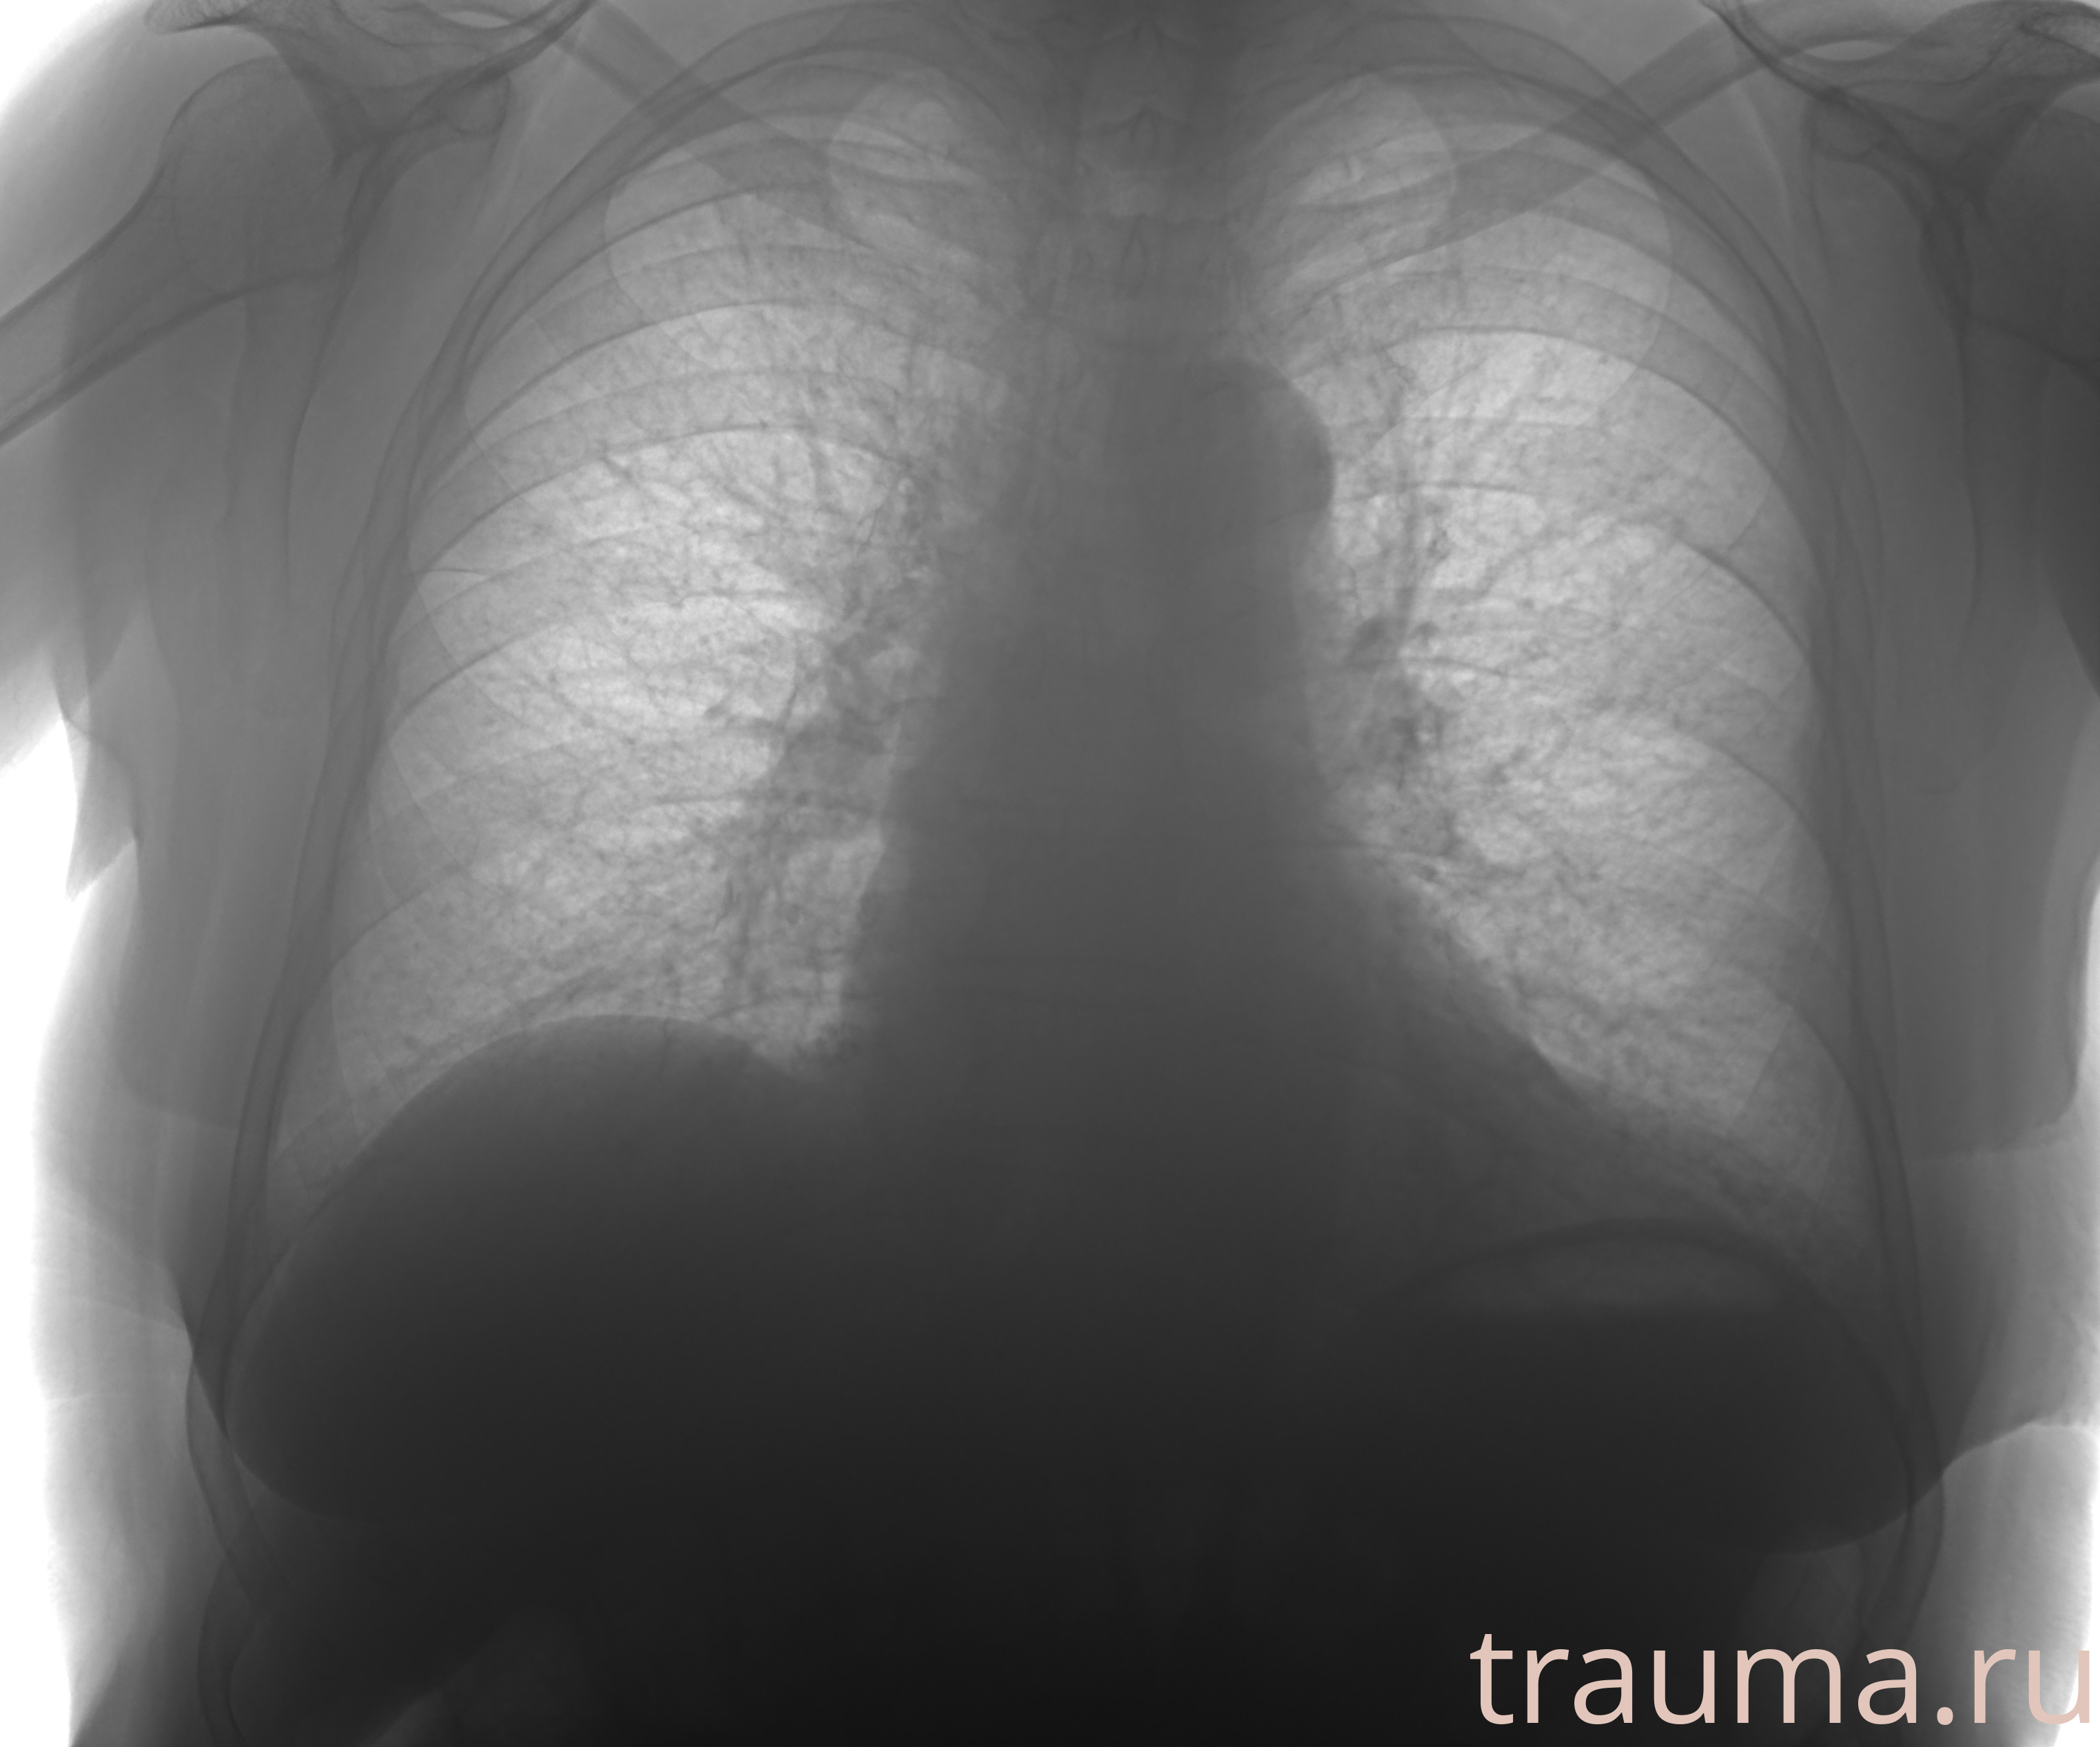

Рентгенограммы

Рентген на дому: по вашему адресу приезжает врач-рентгенолог, травматолог-ортопед с мобильным рентгеновским аппаратом, проводит диагностику травмы или заболевания, делает необходимые рентгенограммы, дает рекомендации по дальнейшему лечению. Получить качественные снимки в домашних условиях возможно благодаря уникальной методике, разработанной МосРентген Центром для института  Склифосовского